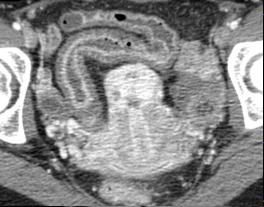

| Image fibrose sclerosant

lipomatose de ilein avec epaissisement marque de sa

paroi. Maladie de Crohn de ileon en coupe TDM axiale

|